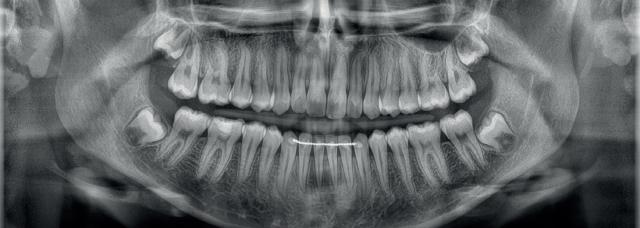

Predictable management of a deep carious lesion, page 27

Managing Editor: James Cooke